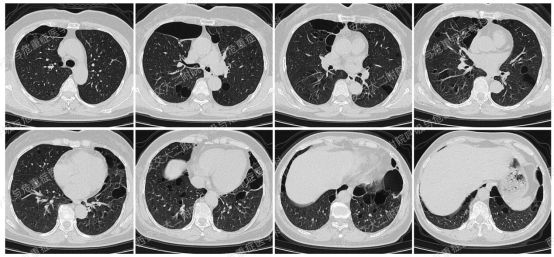

以下2例不同患者的胸部影像改变,又分别考虑什么疾病呢?